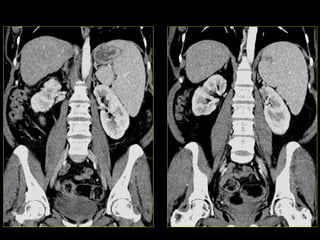

Caso # 2 ♀ , 6ta década de la vida  Estudio de TC para seguimiento y evaluación  de quistes renales.  Se realiza estudio con medio de contraste endovenoso, mostrándose la fase venosa, con cortes axiales y con reconstrucciones multiplanares (RMP) coronales.

Hallazgos Caso #2: Área hipodensa triangular en polo superior del riñón izquierdo, en relación con proceso inflamatorio lobar renal.